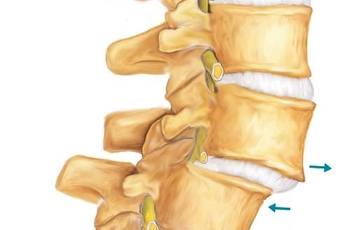

Страдает хрящевая ткань фиброзного кольца межпозвоночного диска. Оно обезвоживается, деформируется и теряет свою привычную высоту. Возникает свободное натяжение связок и сухожилий. Тело позвонка начинает более свободно ротироваться в образовавшемся промежутке. Поэтому при нестабильности положения тел позвонков необходимо искать нарушение диффузного обмена и снижение высоты межпозвоночных дисков. За исключением тех случаев, когда спондилолистез вызван растяжением связочного аппарата и деформацией унковертебральных суставов.

- уменьшение высоты межпозвоночного диска, в результате этого возникает нестабильность положения тел позвонков;

- между тела позвонков располагаются хрящевые межпозвоночные диски (состоят из фиброзного кольца и пульпозного ядра, обеспечивают амортизацию и не допускают столкновения позвонков между собой);

Хрустит позвоночник в пояснице, грудном и шейном отделе

Чаще всего хрустит позвоночник в пояснице и звук появляется при наклонах и выпрямлениях туловища. Это клинический признак протрузии межпозвоночного диска. Обезвоживание фиброзного кольца приводит к уменьшению объема пульпозного ядра. В результате возникает нестабильность положения тел позвонков. Важно своевременно проводить лечение, направленное на укрепление связочного аппарата и увеличение высоты межпозвоночного диска.

Основная причина хруста — уменьшение высоты межпозвоночных дисков